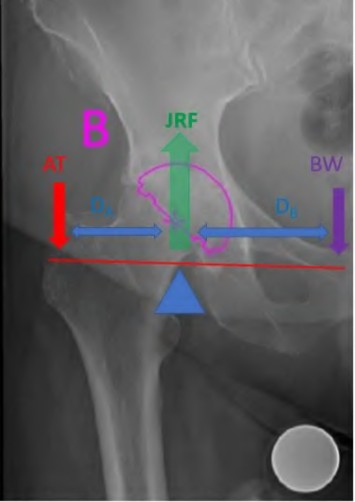

During a total hip arthroplasty, the surgeon utilizes a standard offset stem instead of a high offset stem, inadvertently decreasing the patient's native femoral offset by 15 mm. What is the most likely biomechanical consequence of this error?

Explanation

During a primary total hip arthroplasty, the surgeon opts to increase the femoral offset compared to the patient's native anatomy. Assuming the leg length is kept constant, which of the following biomechanical effects is most likely to result from this change?

Pre-operative templating for a primary total hip arthroplasty aims to restore native femoral offset. Failure to restore femoral offset (leaving it decreased) leads to which of the following biomechanical consequences?